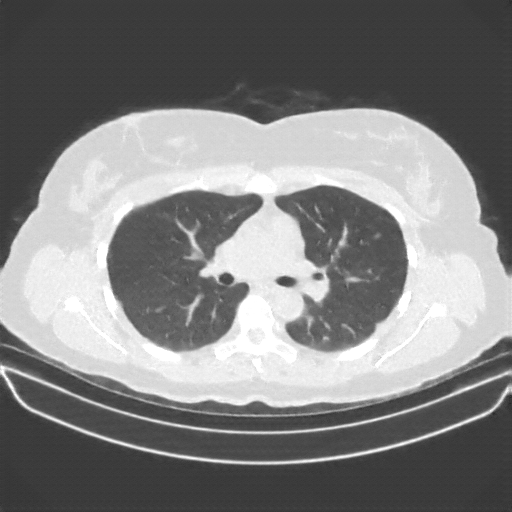

Image Grid

4Γ—3 grid: Rows show different image types (Original NATIVE, Reconstructed NATIVE, Original VENOUS, Generated VENOUS), Columns show windowing techniques (No Window, Lung Window, Mediastinum Window)

Original NATIVE CT scan (input)

No window - Raw intensity values

Lung window (WL -600, WW 1500 β†’ Low βˆ’1350, High +150)

Mediastinum window (WL 40, WW 400 β†’ Low βˆ’160, High +240)